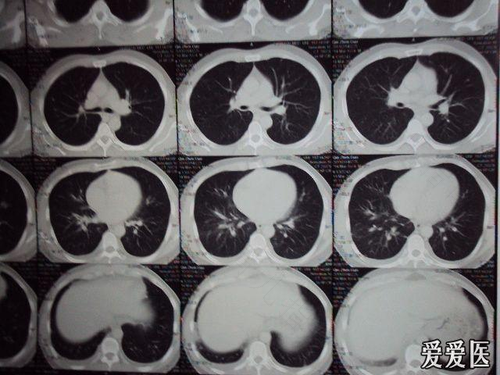

患者的情况是,长时间咳嗽,现在觉得咳嗽时,胸部会疼痛,可能是咳嗽震动引起的胸膜疼痛,也可能是其他原因导致的,需要用药物进行治疗,可能还是没有治疗彻底,建议再继续用几天药,看效果如何。疼痛属于慢性炎症刺激引起的。需要注意休息观察。一般很快可以恢复。如果一周不恢复,检查胸部CT看一下。